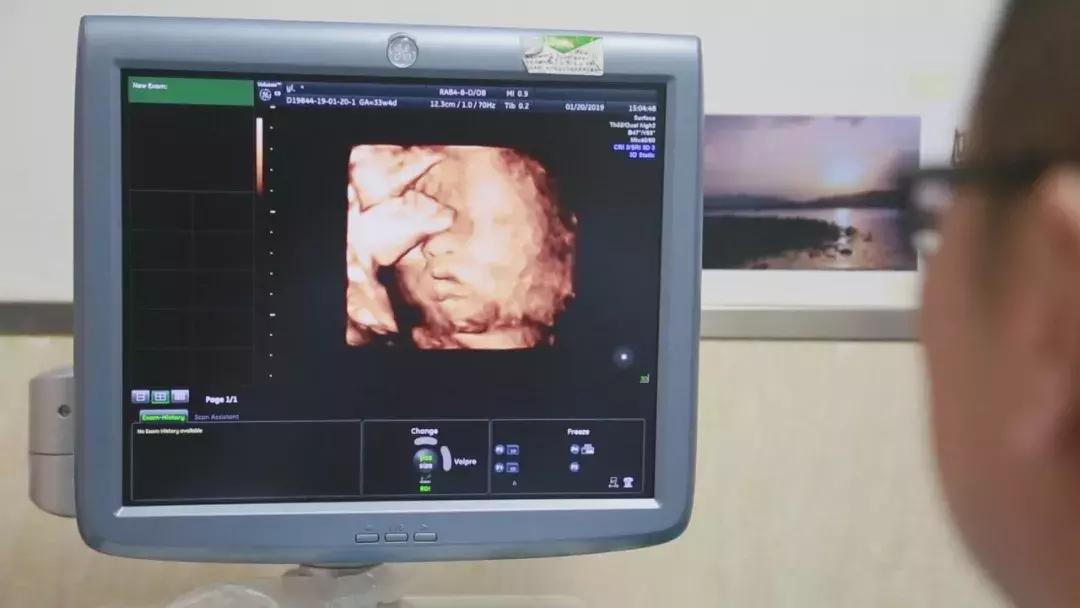

在对移植子宫连续监测后,为提高胚胎移植成功率,专家团队采取中西医结合的方法,改善杨华子宫内膜情况,为胚胎着床做好准备。2018年6月13日,妇产科王西林教授实时监测超声,在超声“慧眼”精确指引下,妇产科黄艳红教授小心翼翼地将冷冻胚胎植入移植的子宫内。14天后,复苏胚胎着床,杨华成功妊娠,这已是第五次尝试。妊娠早期,杨华出现妊娠剧吐、先兆流产的症状,妊娠中晚期出现胎儿生长受限,先后4次住院进行保胎等治疗。

足月的胎儿对移植子宫导致的压力,让分娩的风险成倍增加,陈必良教授团队选择在孕33+6周进行剖宫产手术,迎接这个新生命的到来。2019年1月 20日,陈必良教授主刀施行剖宫产手术,刘朵朵教授配合手术,麻醉科陈敏教授施行麻醉。术中,采取腹壁纵切口完成子宫下段剖宫产,探查确认移植的子宫动静脉缝合口、韧带等恢复良好,手术历时1小时6分钟圆满成功。新出生的宝宝身体各指标正常,体重2kg,身长48cm,Apgar’s评分:1分钟10分,5分钟10分,10分钟10分。剖宫产手术结束后,专家团队没有立即摘除子宫,小两口还计划着孕育二胎。